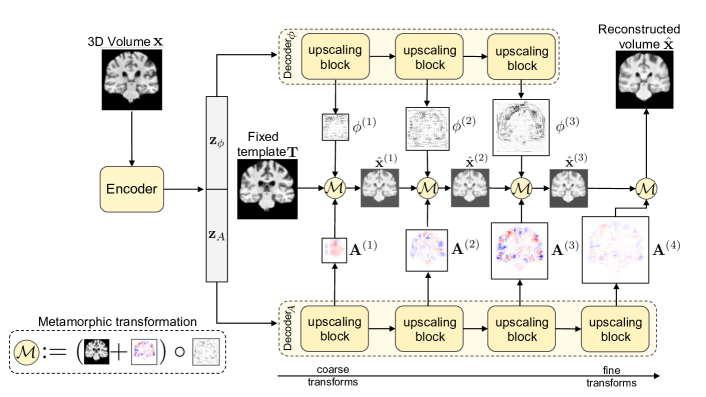

The proposed model, which we term multiscale metamorphic autoencoder (M3AE) is based on the standard VAE. However, instead of direct pixelwise outputs, our model outputs morphological transforms that map a fixed standard template to the input image . If the template image is sufficiently similar to , the generation task may be substantially simpler than generating images ‘from scratch’. We use two classes of transforms: deformations and additions. The diffeomorphic transform , where the deformation field is applied as in the LDDMM framework [1], performs non-affine elastic deformations, which captures atrophy patterns and structural variations. The intensity transformation is an additive transformation , and is expected to capture subject and scanner-specific intensity variations, lesions, and topological irregularities. The two transforms can be composed into metamorphic transformations [5, 17], denoted as .

We then apply these transforms in a cascaded, multiscale fashion at increasing scales. For generation, the decoder is split into two backbones – Decoderϕ and DecoderA (Fig. 1). Each decoder, made up of upscaling blocks, is given a subset of as input (i.e., / to Decoderϕ / DecoderA, respectively) and outputs a corresponding set of coarse-to-fine transform parameters . By composing coarse and fine transforms in an interleaved fashion as illustrated in Fig. 1, we obtain more expressive transformations and hence better coverage of the data space. The last transformation is only additive in nature and outputs the final reconstruction . The loss function, , for training the model can be written as

In Eq. 1, is the VAE [8] loss, and consists of intermediate regularization and reconstruction loss terms for the th transform level. To ensure appropriate behaviour of the transformation cascade, we constrain intermediate volumes to be close to the final volume at each level (first term in Eq. 3). The transformation parameters are regularized using decay terms for , and spatial gradient and divergence minimizers for . are hyperparameters to appropriately scale the loss terms.